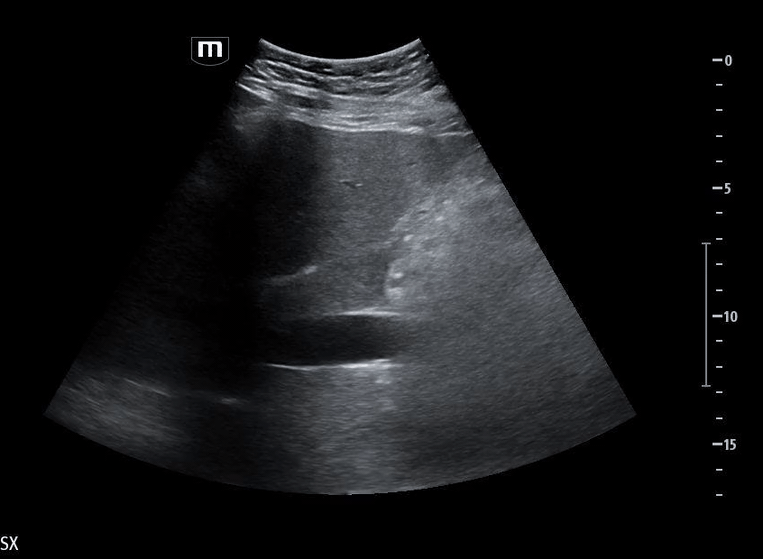

She isn’t crashing—but she isn’t stable either. Luckily, an ultrasound is immediately available. An eFAST exam is performed, revealing the following:

Image 1 demonstrates the left lung view with absence of lung sliding.